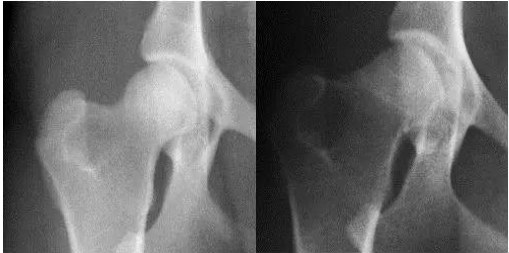

2006年3月9日,美国专利Kolla 2 研究团队经过临床试验证明服用【骨精华】主要成份II型骨胶质(kolla2)六周后,患有关节发育异常的犬科动物恢复了正常运动功能,随后的X光射线显示髋关节软骨明显增厚,恢复正常。以下为服用II型骨胶质Kolla2前、后X光对比图: